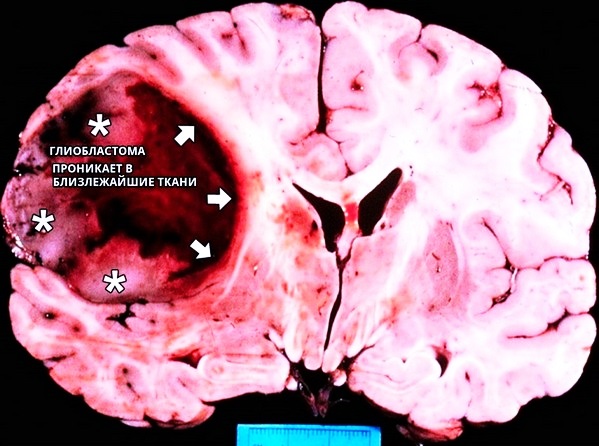

Глиоматоз относится к первичным опухолям мозга. Внешне образование розовое, сероватое или красное, объемное. Имеет вид узла. Границы нечеткие.

Чаще всего глиома головного мозга единична. Может наблюдаться диффузное поражение, развитие отека. Располагается она в преимущественном большинстве ситуаций в сером либо белом веществе головного, спинного мозга. Новообразования могут крайне близко находиться возле центрального канала и стенок желудочков. В периферических нервах образования локализуются намного реже.

Иногда опухоль может локализоваться в зрительном нерве. Очень редко она прорастает в оболочки мозга, кости черепа. При этом она буквально сливается со здоровыми тканями, приводит к их дегенерации. Помощь в таких случаях сводится к облегчению состояния. Выживаемость минимальна.

По форме глиома напоминает шар, реже – веретено. Растет она достаточно медленно. Заболевание может развиваться на протяжении нескольких лет. При возникновении глиобластомы метастазы не появляются. Прогнозирование сугубо индивидуально.

Основной метод лечения глиомы – хирургическое удаление. Это очень опасно, так как могут повреждаться важные отделы мозга или проникает инфекция. Нейроэпителиальная ткань трудно удаляется, так как она буквально прорастает в здоровую. Она трудно поддается купированию. Если состояние пациента нестабильное, есть другие опухоли, новообразование располагается в обоих полушариях или расположено неоперабельно, если поражен спинной мозг – это все является противопоказанием для операции.